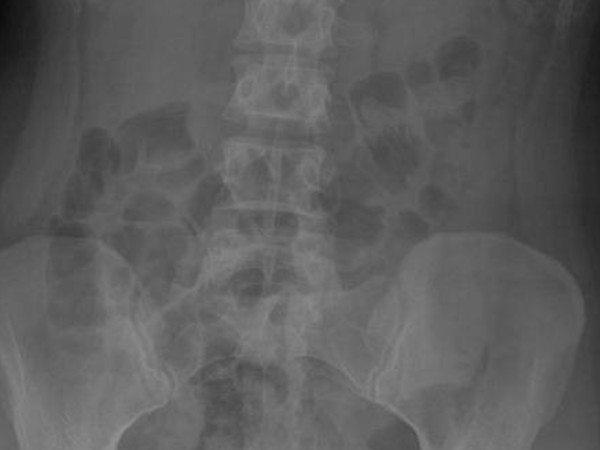

Dette er røntgenbildet mitt av tykktarmen med avføring under undersøkelsen.

“Tjukktarmen din er svært blokkert, med meir enn 5 kg avfall som har hopa seg opp. Testane har vist høge nivå av giftstoff i blodet ditt, og den konstante belastninga har byrja å skade veggane i tjukktarmen. Dersom du ikkje byrjar å få dette bort, kan det føre til farlege komplikasjonar. Du må forstå at tarmen din berre trekkjer seg saman annakvar dag; kroppen din er fysisk ute av stand til å kvitte seg med denne avføringa. Dersom du ikkje blir operert snart, vil du måtte få næring intravenøst.”